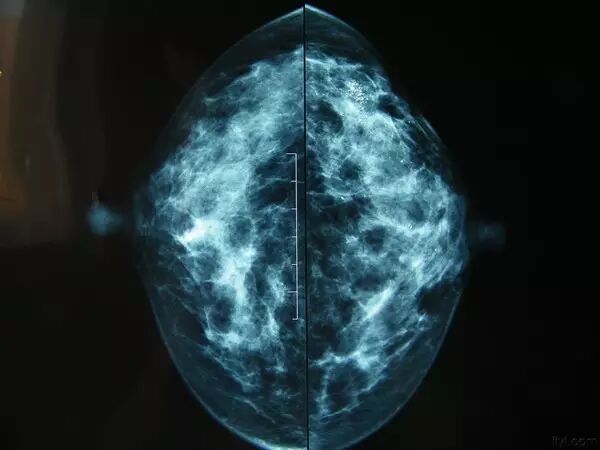

乳腺的检查一般包括彩超、钼钯和磁共振。

适合所有年龄段的女性检查,彩超价格相对低廉,对人体几乎没什么影响,对乳腺结节的敏感性比较高。

对乳腺结节的敏感性更高,同样没辐射,一般彩超下不能确定良恶性的结节会求助于磁共振检查,但同时磁共振价格比价昂贵,是彩超价格的十倍以上,所以一般不作为乳腺常规检查的首选。